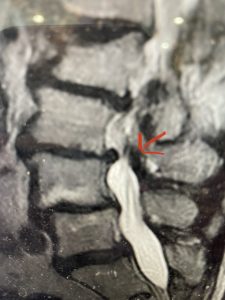

(Fig 2) Sagittal T2-weighted lumbar MRI demonstrating (arrow) tight lateral recess stenosis

This 57 year-old male had a long history of low back pain and left lower extremity pain and numbness. The patient had failed conservative treatment of physical therapy and epidurals. MRI revealed tight left L2-3 and L3-4 lateral recess stenosis as well as significant right L4-5 facet arthropathy and right lateral recess stenosis as well as a grade 1 L4-5 spondylolisthesis